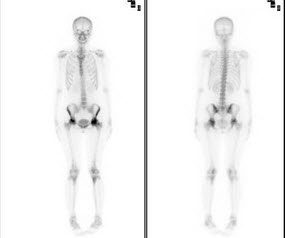

5、多项选择题

男,肝癌术后半年,诉胸背痛3个月,行Tc-MDP骨显像如图,可能的诊断是()

A.大致正常影像

B.胸12骨转移瘤

C.右侧第9后肋“冷区”

D.右侧第9后肋转移瘤

E.右侧第9后肋“甜面圈”征象